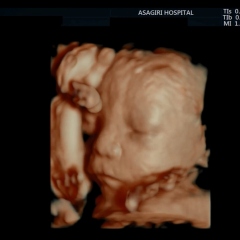

無料体験健診~最新の4Dエコー体験!~ (10/20(木)14:00~)

場所:あさぎり病院産婦人科外来

対象:妊娠12週以降の妊婦の方【要事前予約、先着5名まで】

申込方法:asagiri@asagiri-hp.or.jp(あさぎり病院 総務課)

・胎児4Dエコー